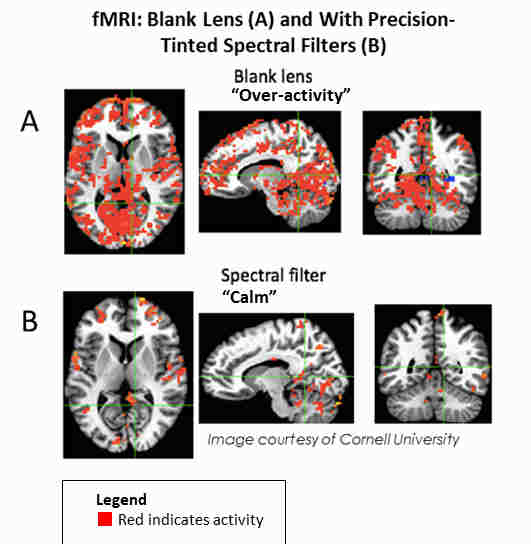

Individuals with Irlen syndrome will often complain of light sensitivity associated with sunlight, bright lighting, fluorescent lights, headlight and glare. They may also have reading problems, as reading becomes inefficient and they may need to re-read for comprehension or build breaks into reading. High contrast (black print on white paper) and visually-intensive activities, create high levels of stress for the brain that trigger physical symptoms which may include headaches and migraines. Brain imaging, both SPECT scans and fMRI, of individuals with this condition shows over-activity, complex brain patterns and non-normalised functioning. This results in a variety of issues, including difficulties reading because of a lack of print stability, issues with glare or discomfort from the white background on the printed page, problems with depth perception and physical symptoms, such as headaches, nausea, dizziness, brain fog, anxiety, strain and fatigue.

Over 100 scientific studies on the topic have established a hereditary component of the disorder1-3, a number of biochemical markers for problems associated with Irlen Syndrome4-6, and differences in brain function between individuals with and without the condition7-11. Precision-tinted colored filters have been found to normalise abnormal brain activity and eliminate issues with print clarity and stability, physical symptoms, and light sensitivity associated with the condition12-21. Although originally thought to be associated solely with reading problems, research has linked visual processing difficulties to a range of other disorders, including ADHD (attention deficit hyperactivity disorder), ASD (autism spectrum disorders), learning disabilities, anxiety and certain emotional and psychological issues22-24. Visual processing challenges also overlap with other neurological conditions, such as migraines and tourette’s8, 25.

Ongoing research by Drs. Adam Anderson and Eve De Rosa at Cornell University’s fMRI facility in the United States shows over-active brain function when Irlen Syndrome sufferers wear a blank lens that normalises when the proper precision-tinted colored filters are worn.